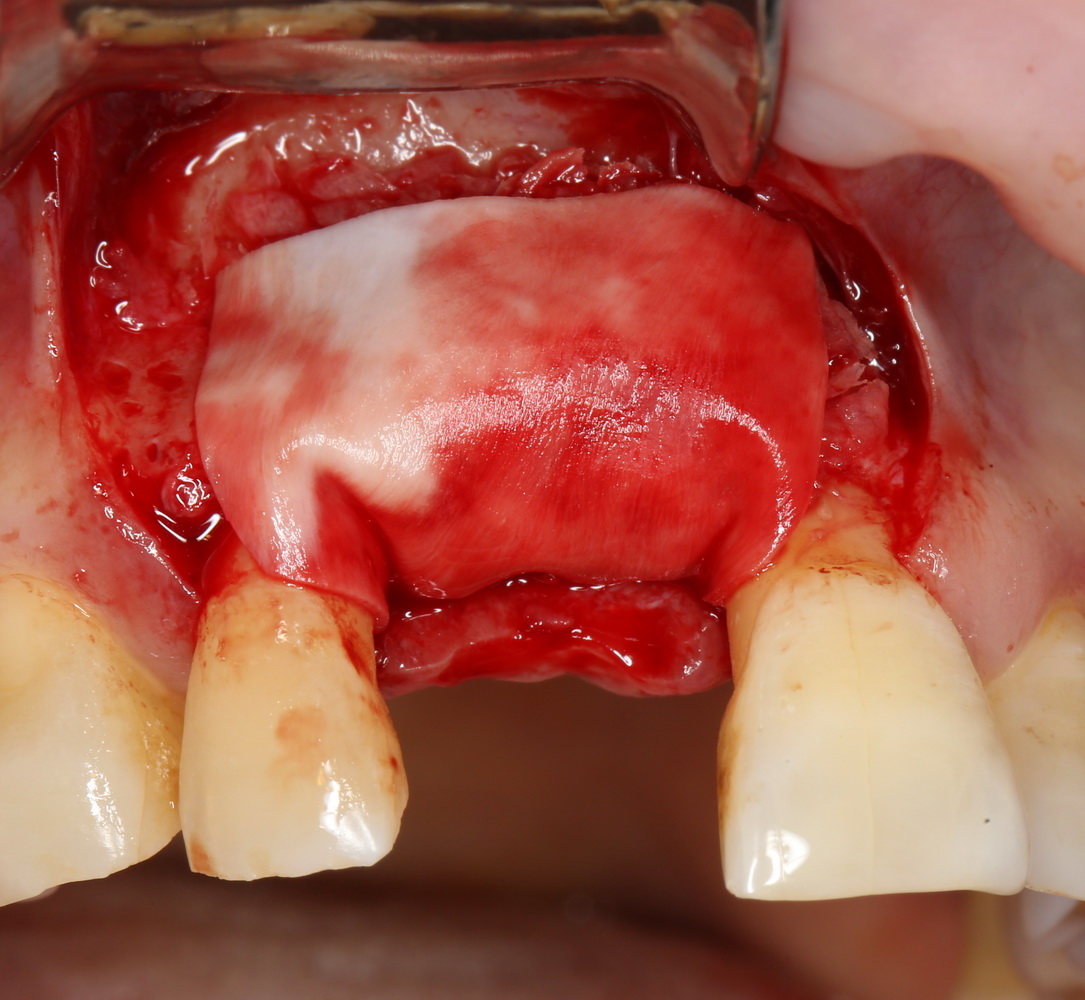

Другой вариант. Имплантируем, но существующего объема костной ткани недостаточно для получения адекватного эстетического и функционального результата:

Поэтому мы используем мембрану Geistlich BioGide и всё ту же аутокостную стружку:

Вот чем мне нравится мембрана BioGide — так это своими свойствами. Предсказуема до мелочей.

Во влажном состоянии она эластична и податлива, поэтому нет необходимости использовать пины или винты: